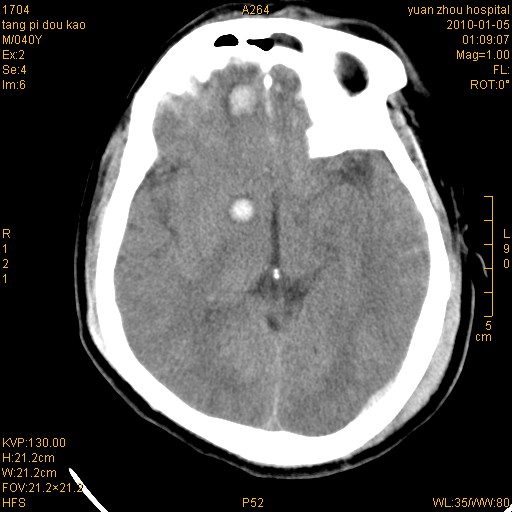

标题: CT23986:M 40Y 外伤数小时

双侧额叶 右侧大脑脚区多发血肿伴蛛网膜下腔出血!

右额叶脑挫伤,脑内血肿形成。左顶枕硬膜外血肿。

1)左侧颞枕部硬膜外血肿。2)右侧额部硬膜下血肿。3)双侧额叶及右侧基底节下部脑挫裂伤。4)蛛网膜下腔出血。5)脑水肿。6)左侧前组筛窦及左侧额窦炎症。

前纵裂池的出血是硬膜下还是蛛网膜下腔?右额叶深区血肿还是基底节血肿?